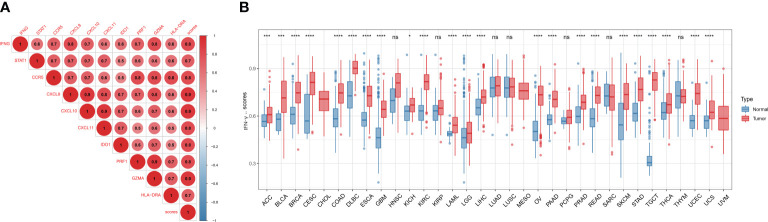

Differential expression of IFN-γ score and its association with tumor staging

Firstly, we found a positive link between genes associated with IFN-γ (p<0.05), indicating a close association between IFN-γ-RGs (f4). We also assessed the IFN-γ score between tumor and normal specimens for 33 malignancies using data from GTEx and TCGA. In contrast with normal samples, IFN-γ scores were remarkably elevated in carcinoma tissue samples, including in UCS, BRCA, UCEC, COAD, TGCT, OV, LIHC, LAML, PAAD, KIRC, PRAD, GBM, LGG, READ, ESCA, SKCM, DLBC, STAD, CESC, THCA, BLCA, and ACC. Twenty-two of thirty-three tumors had IFN-γ scores that were greater than those of normal tissues, implying that the inflammatory response in cancerous tissues was greatly enhanced (f4). The IFN-γ scores in pan-cancer at different stages were further investigated. The IFN-γ score was remarkably higher in the early stages of TGTC, HNSC, and COAD (All P < 0.05). The score of IFN-γ was higher in the late stage of KIRP (All P < 0.05). It can be inferred that IFN-γ may be a breakthrough in the early prevention and treatment of TGTC, HNSC, and COAD (Supplementary Figure 2).